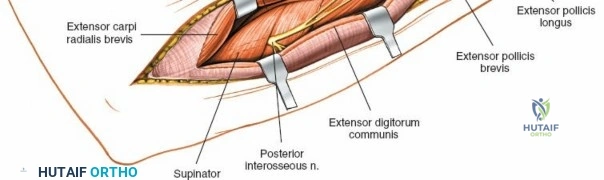

Superficial Surgical Dissection and Internervous Plane

Incise the deep fascia of the forearm in line with the skin incision. The initial goal is to identify the medial border of the brachioradialis as it courses down the forearm. It is a common pitfall to search for this border too far laterally. At the level of the elbow, the brachioradialis is expansive and extends almost halfway across the anterior forearm. It is surprisingly easy to mistake the plane between the brachioradialis and the extensor carpi radialis longus for the correct intermuscular plane.

To confirm the correct plane, look for the superficial branch of the radial nerve. This sensory nerve runs on the undersurface of the brachioradialis muscle. Once the true medial edge of the brachioradialis is found, develop the plane between it and the pronator teres (proximally) or the flexor carpi radialis (distally). Retract the brachioradialis laterally, taking care to keep the superficial radial nerve attached to its undersurface to protect it from traction injury.

Deep Surgical Dissection: Exposing the Proximal Third

Exposing the proximal third of the radius requires extreme vigilance due to the proximity of the posterior interosseous nerve. The key anatomical landmark here is the insertion of the biceps tendon. Follow the biceps tendon distally to its insertion on the bicipital tuberosity of the radius. A small bursa lies just lateral to the tendon; incise this bursa to gain initial access to the proximal radial shaft. Because the radial artery lies superficial and medial to the tendon at this level, all deep dissection must remain strictly lateral to the biceps tendon.

The proximal radius is draped by the supinator muscle. The PIN passes directly through the belly of the supinator. To protect the nerve, the forearm must be fully supinated. Supination dynamically rotates the radius, carrying the insertion of the supinator anteriorly and simultaneously displacing the PIN laterally and posteriorly, safely away from the surgical field.

With the forearm fully supinated, identify the broad insertion of the supinator on the anterior aspect of the radius. Incise the supinator directly along the line of its insertion onto the bone. It is critical to detach the muscle by dividing its insertion sharply at the bone, rather than splitting the muscle belly, which would risk cutting the PIN.

Proceed with strict subperiosteal dissection, elevating the supinator laterally off the bone. This is one of the rare instances in orthopedic surgery where the safety gained by staying in a subperiosteal plane completely outweighs the theoretical vascular damage to the bone caused by periosteal stripping. The elevated supinator muscle belly now acts as a protective cushion for the PIN.

Retractor Placement and Fixation Technique

Once the proximal radius is exposed, great care must be taken with retractor placement. Never place Hohmann or levering retractors blindly around the posterior surface of the radial neck. Because the PIN may touch the bone posteriorly in up to 25% of patients, a posteriorly placed retractor can easily crush the nerve against the radial cortex. Instead, use gentle right-angle retractors or place retractors only on the anterior and lateral aspects of the bone, utilizing the elevated supinator as a shield.